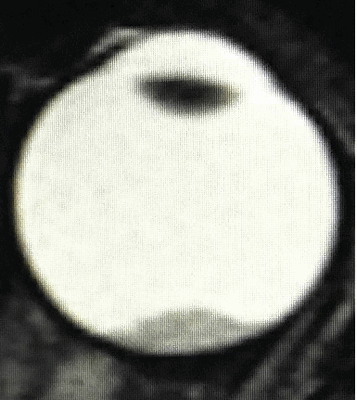

- В - остальные опухоли, располагающиеся отдельно, ограниченные сетчаткой с вероятным наличие субретинальной жидкости в не более чем 3 мм от основы опухоли, не сопровождающееся субретинальным обсеменением (рис. 2).

![Визуализация ретинобластомы с помощью МРТ. Клиническая группа В]()

Рис. 2. Визуализация ретинобластомы с помощью МРТ. Клиническая группа В